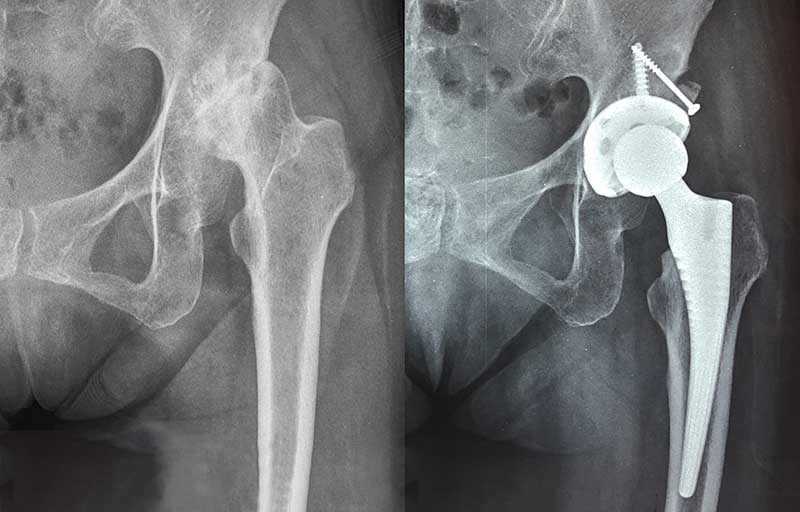

Operasi penggantian sendi panggul adalah operasi yang dilakukan untuk mengganti sendi panggul yang telah mengalami kerusakan akibat pengapuran dengan sendi panggul buatan. Panggul merupakan sendi kedua tersering setelah lutut yang paling sering terserang pengapuran sehingga operasi penggantian sendi penggul merupakan operasi penggantian sendi yang paling banyak dilakukan setelah penggantian sendi lutut.

Operasi penggantian sendi panggul bermanfaat menghilangkan nyeri sendi akibat pengapuran sendi dan memperbaiki gaya jalan pincang akibat nyeri panggul tersebut.